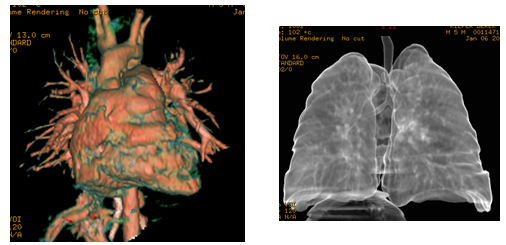

CT is still an important tool in pediatric diagnosis. New technology has evolved to dramatically lower the radiation dose of CT scans in children. Additionally, the CT scans can now be performed very quickly. In the past, some children would need to be sedated with medication in order to insure that they could hold still long enough for the test to be performed. The new ultrafast CT scanners are so fast that sedation is often unnecessary.

3D reconstruction of a CT scan in a patient with a double aortic arch squeezing the trachea (windpipe) causing him breathing difficulty.

3D reconstruction of a CT scan in a patient with a double aortic arch squeezing the trachea (windpipe) causing him breathing difficulty.